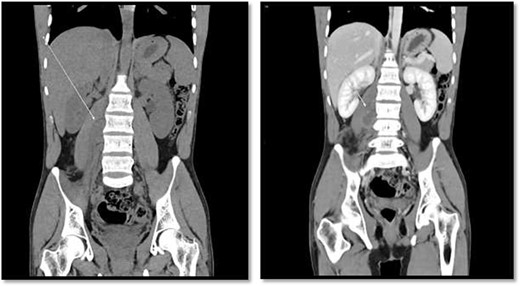

Scrotal Doppler ultrasound shows the size, echogenicity and vascularity is maintained for both testicle with slightly reduced in the right testicle that could be suggestive of right torsion/detorsion.

An 18-year-old healthy man presented to the emergency department (ED) with 1-day history of right testicular pain and vomiting with no fever nor abdominal pain. Physical examination showed mild tenderness in the right testis, no swelling, normal longitudinal position and cremasteric reflex. Scrotal Doppler ultrasound was performed and showed reduced vascularity in the right testis and the left testis was normal. Moreover, the size and echogenicity were maintained for both testes (Fig. 1). Two months prior to this presentation, the patient presented with the same attack with only mild tenderness in the right testis, and all investigations were within normal limits and he was discharged with oral analgesic drugs. The decision was made to undergo surgical exploration for possible torsion/detorsion of the right testis. The patient was transferred immediately to the operating room for bilateral orchiopexy. The right spermatic cord was engorged with no evidence of ischemia identified and bilateral orchiopexy was done successfully. After the surgery, the patient was kept for observation for 24 h and then discharged. After 2 days from the surgery, the patient came back to ED with testicular pain and post-surgical swelling. We decided to do computerized tomography (CT) scan of the abdominal and pelvis to rule out retroperitoneal pathologies or referred pain. The CT showed 4 × 3 cm lobulated mass noted at right paravertebral space invading the right psoas muscle at the level of L3 and L4 (Fig. 2). The CT scan also showed there is an associated fistula tract between the mass and infrarenal inferior vena cava with thrombosis associated with epidural component extending through the neural foramina compressing the spinal cord from the level of the L2–L4 (Fig. 3). The patient was referred to spinal surgery and CT-guided paraspinal lumbar biopsy was taken. The histopathology came with the diagnosis of Ewing sarcoma. The decision was made by the medical oncology to start on a systemic chemotherapy (vincristine + Adriamycin + cyclophosphamide alternating with ifosfamide + etoposide (VAC/IE)) regimen. After six cycles, the follow-up magnetic resonance imaging demonstrated significant resolution of the right psoas and posterior paraspinal metastatic disease. In addition, further resolution with residual intraspinal extradural metastatic disease noted at right L2–3 and L3–4 levels. The patient is still followed up as an outpatient clinic with medical oncology.